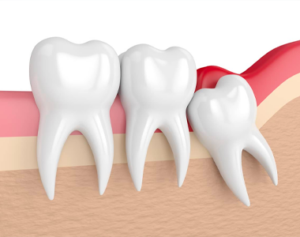

With age comes wisdom. Specifically, wisdom teeth. Your mouth goes through many changes in your…